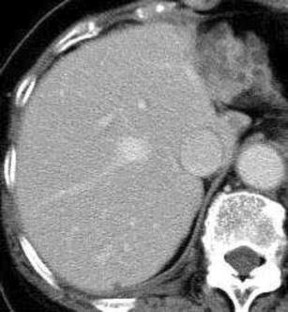

We herein report a case of monolobar hepatobiliary fibropolycystic disease. A 75-year-old woman presented with heartburn. Imaging modalities including US, CT, and MRI revealed marked atrophy and multiple biliary cysts of the hepatic left lobe. The hepatic right lobe was normal. ERCP and bile duct endoscopy revealed anomalous pancreaticobiliary union, choledochal dilation, dilation of left intrahepatic bile ducts, and small choledochal non-invasive adenocarcinoma. Polycystic kidney diseases were absent. The patient underwent pancreatico-duodenectomy and extended hepatic left lobectomy. Grossly, the hepatic left lobe was markedly atrophic, and studded with numerous biliary cysts. The left intrahepatic bile ducts were dilated (Caroli’s disease) and the common bile duct showed type I choledochal dilation. The right hepatic lobe was normal. Histologically, the hepatic left lobe was replaced by fibroelastosis. The intrahepatic bile ducts showed ductal plate malformation such as irregular contours, invaginations, and protrusions. The numerous biliary cysts also showed ductal plate malformation. There were numerous persistent ductal plates and microhamartomas. Many hyalinized destructive biliary cysts and ductal plates were recognized. The liver parenchyma was scant and free of hepatocellular malformations. The portal veins showed old obliterative portal thrombosis. The right hepatic lobe was normal. Immunohistochemically, the biliary cells were positive for cytokeratin 7, 8, 18 and 19, and MUC6 and CD10, but negative for MUC2 and MUC5AC. The biliary cysts, persistent ductal plate, and microhamartomas were positive for fetal apomucin antigen MUC1.

Fig. 2